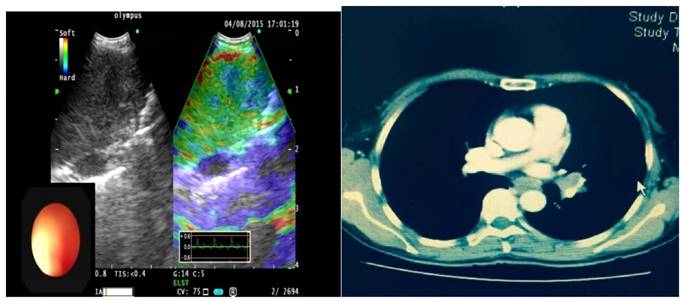

As one result of this study we found false positive LNs in the Type 3 group classified histologically as sarcoidosis [Figure 2], due to fibrous tissue hyperplasia in lymphoid tissue leading to increased hardness. For false negative patients in type 1 lymph nodes, the final pathologic result was adenocarcinoma [Figure 3], because the lymph node invasion by tumor cells caused partial lymphoid tissue liquefaction. Due to the above-mentioned reasons, operators should combine clinical examination with patients medical history in order to avoid misdiagnosis. There are two groups of patients; one is tuberculosis patients, with caseous necrosis and more calcifications which increase organization hardness. The second is chronic lymphadenitis patients: Here the tissue hardens by increased fibrous tissue hyperplasia. In these 2 groups the operator should pay high attention during EBUS elastography examination of superficial lymph nodes.

Figure 2

A case of 4R with Type 1 lymph node on EBUS elastography, pathological results show scattered granulomas, did not clear tumor lesions, considering sarcoidosis.